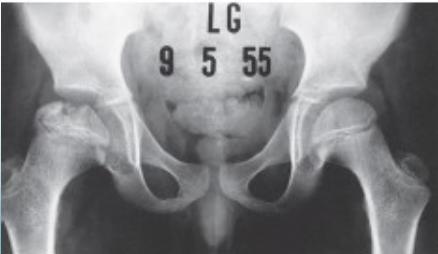

Slipped Capital Femoral Epiphysis (SCFE)

Definition: Antero-lateral slippage of the femoral metaphysis relative to the epiphysis

Imaging:

- Required views: AP and Frog lateral pelvis

- Key finding: Slippage of femoral epiphysis

Radiographic Examples:

Comparative views showing slipped vs. normal hip:

(Source: Apley’s System of Orthopedics and Fractures)

X-ray Diagnosis:

| View | Slipped Hip | Normal Hip |

|---|---|---|

| AP | ![]() | - |

| Frog Lateral | ![]() | - |